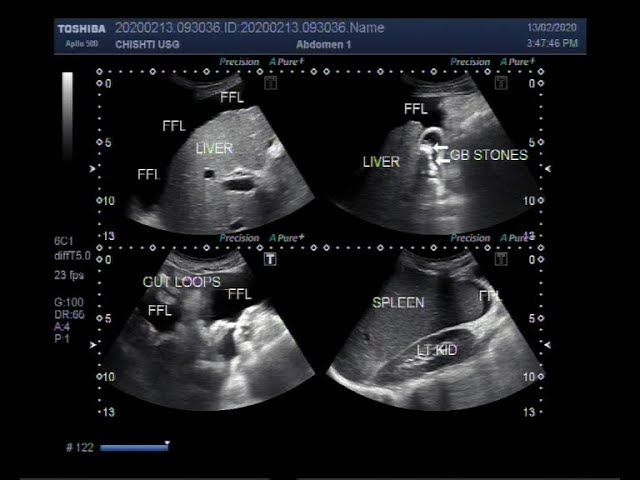

Hình ảnh siêu âm gan (Nguồn: Internet)